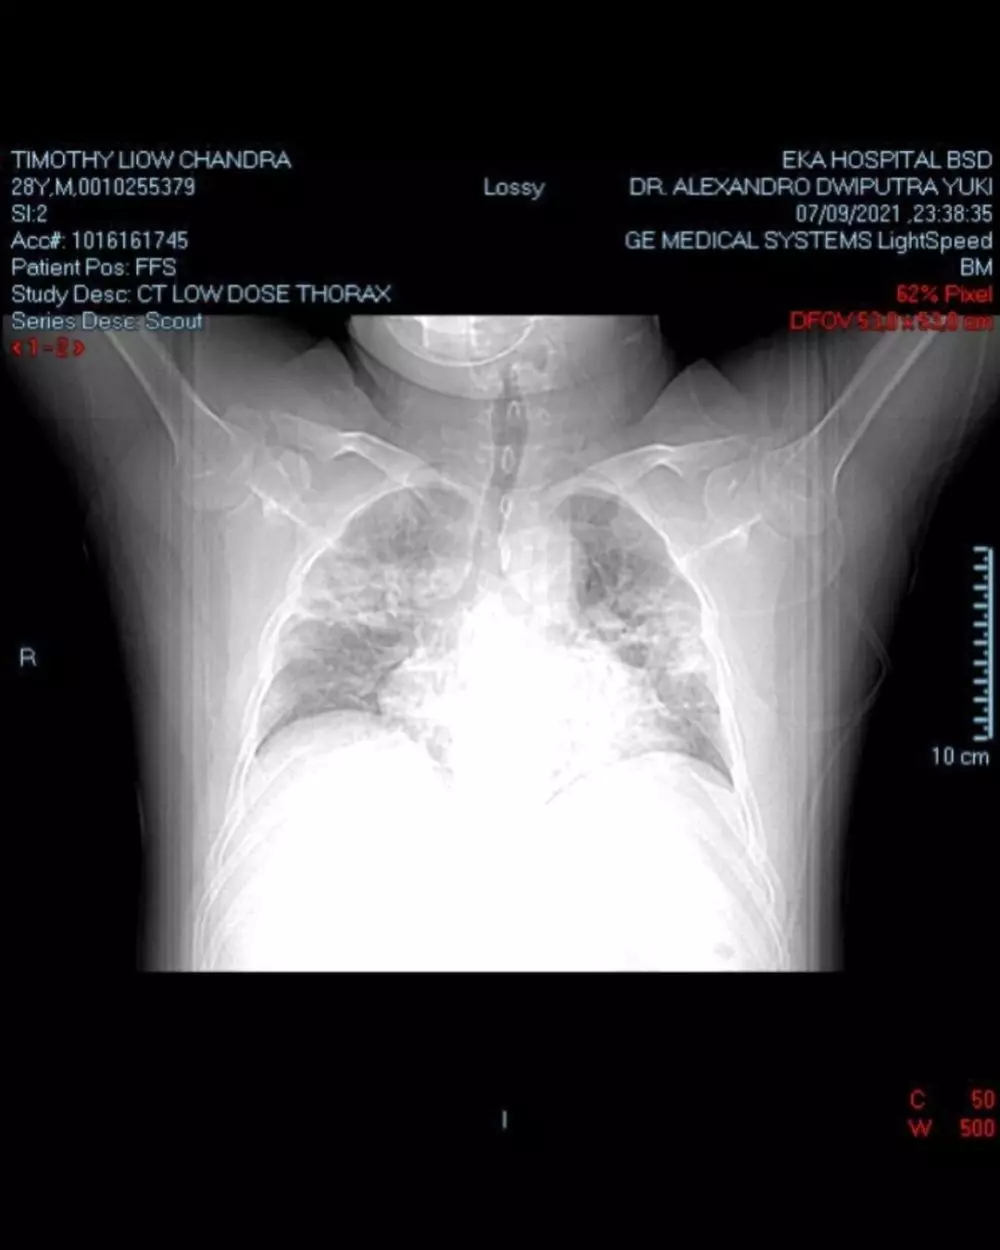

Beberapa potret yang menjadi perjalanan Chandra untuk sembuh dibagikan dalam media sosial itu. Pelantun lagu Sweet Talk itu mengatakan bukan hal mudah untuk bisa terbebas dari virus Covid-19. Pasalnya, virus itu juga menyerang organ hati, jantung, paru-paru, hingga mengakibatkan pengentalan darah di dalam tubuhnya.

"29 Juni positif covid. 9 Juli harus masuk IGD. Badai Sitokin, Hati infected, Jantung infected, Ada pengentalan darah (D-Dimer 1500), Paru-paru infected sudah buram, Nyawa sudah kritis. Dan dokter pun juga sudah keluar kata-kata “harus ikhlas ya.,” kenang Chandra, seperti dilansir brilio.net pada Minggu (12/9).

Sementara itu berjemur dan perawatan fisioterapi terus dijalani untuk mempercepat pemulihan. Berbuah manis, Chandra pun dinyatakan sudah tak memiliki bercak pada paru-parunya. Usahanya untuk sembuh selama 2 bulan itu pun membuatnya begitu bersyukur dapat terselamatkan dari serangan virus Covid-19.